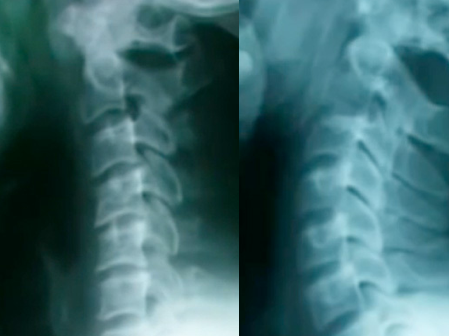

ストレートネックとは、本来ゆるやかに前弯している頚椎のカーブが失われ、首がまっすぐに歪んでしまった状態